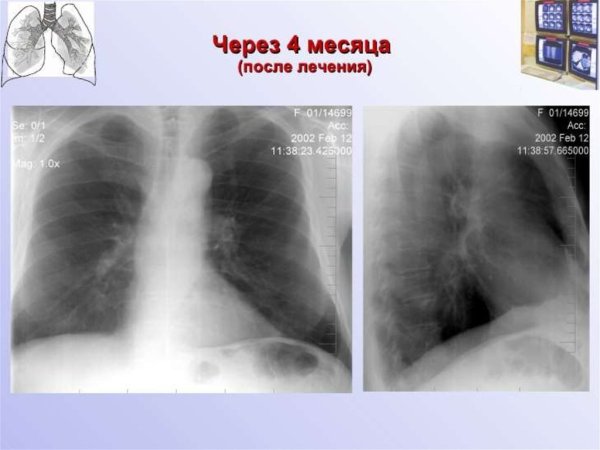

Патология легочного рисунка - это состояние, при котором обнаруживается изменение образца распределения сосудистых и бронхиальных структур в легких. Это может быть вызвано различными причинами, такими как хронические заболевания легких, врожденные аномалии или инфекционные процессы. При патологии легочного рисунка могут наблюдаться различные изменения на рентгенограммах, такие как утолщение сосудов, усиление бронхиального образца или появление тени. Диагностика и лечение этого состояния требуют комплексного подхода, основанного на клинических данных и дополнительных исследованиях. Целью такого лечения является устранение основной причины патологии легочного рисунка и восстановление нормальной структуры и функции легких.